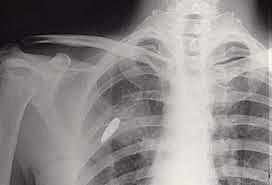

• RADIOGRAFÍA RAYOS X

RADIOGRAFÍA RAYOS X

El descubrimiento llegó el 8 de noviembre de 1895. Mientras estudiaba el poder de penetración de los rayos catódicos, Röntgen observó que una placa de cartón cubierta de cristales de platino-cianuro de bario emitía una fluorescencia, que desaparecía al desconectar de la corriente